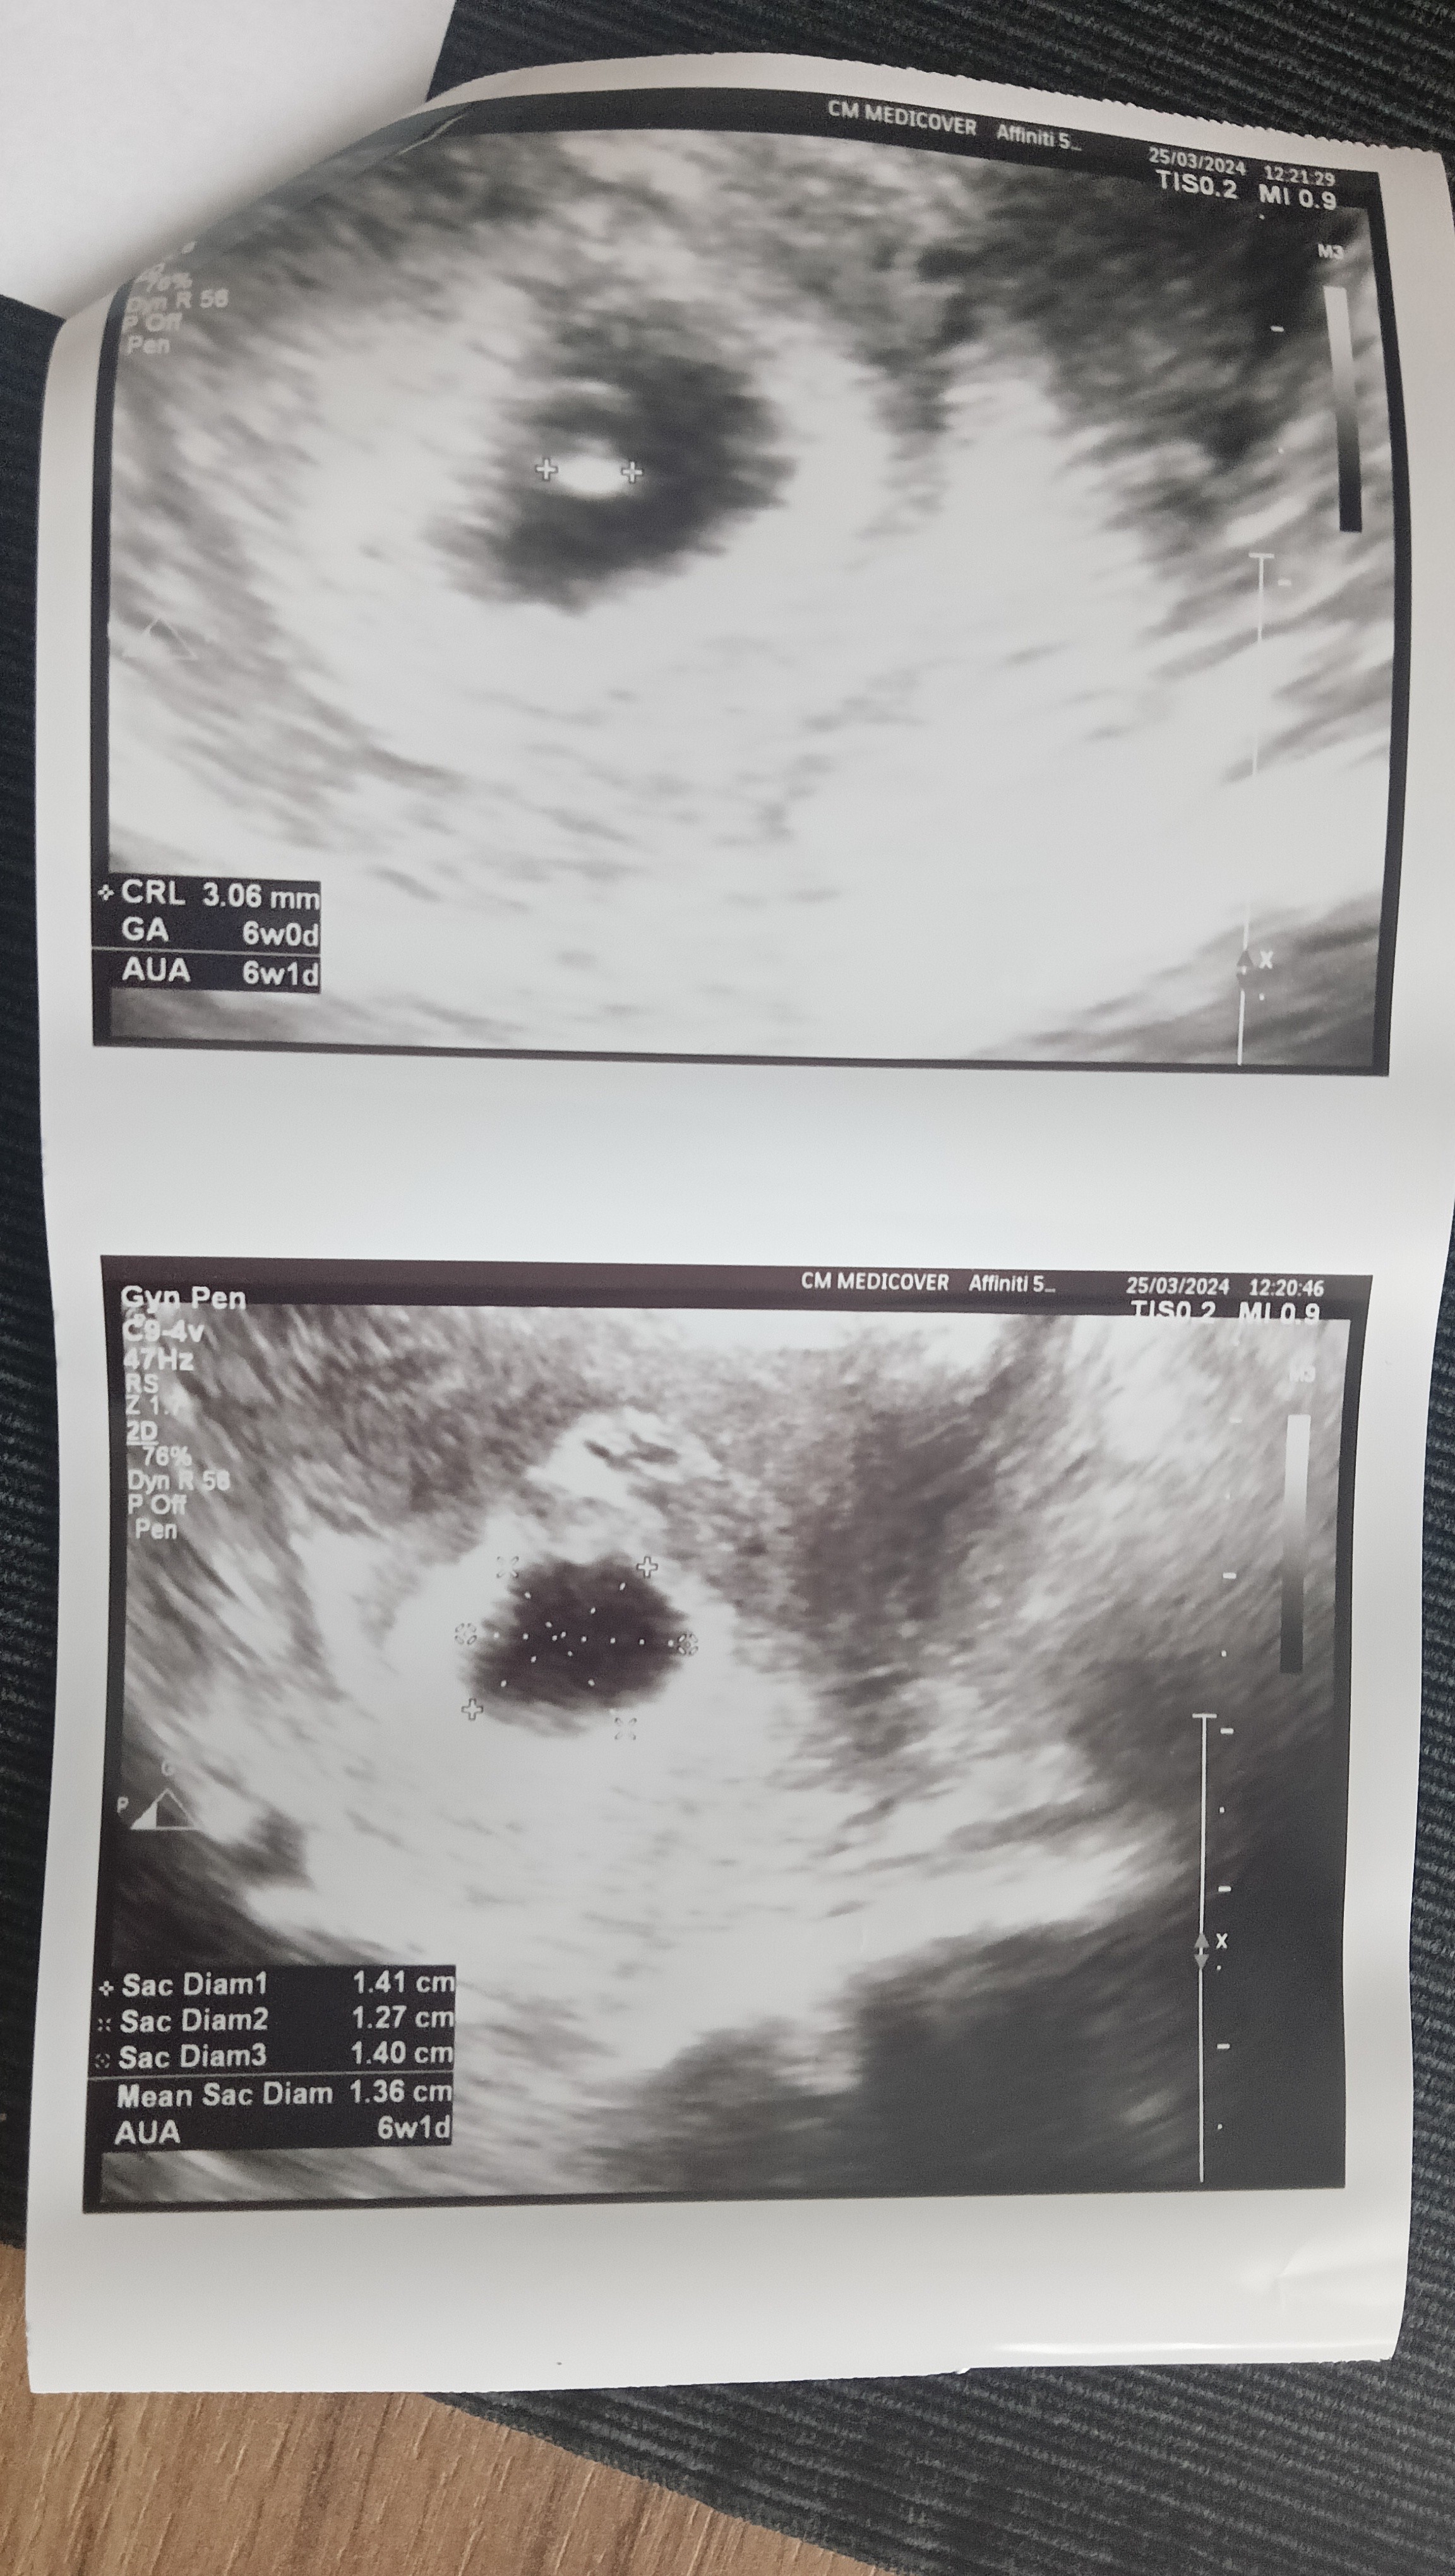

Super! Ja też w tym roku kończę 30. Z tym, że ja już mam córkę 11l.To i ja się w końcu nieśmiało przywitamTo moja pierwsza ciąża, udało się po 3 miesiącach starań, w tym roku kończę 30 lat. OM 14.02, według USG 6t, panu Doktorowi podczas badania udało się uchwycić bijące serduszko